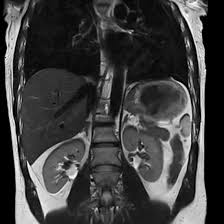

MRI Whole Abdomen

An MRI of the Whole Abdomen is a comprehensive imaging procedure that clearly depicts images of all the organs in the abdomen, such as the liver, kidneys, pancreas, spleen, intestines, and tissues around the abdomen. This is an advanced diagnostic method utilizing magnetic fields and radio waves to produce high-resolution images of the structures with no ionizing radiation to the patients. MRI Whole Abdomen is particularly helpful in diagnosing a wide variety of conditions, including tumors, liver diseases, kidney disorders, abdominal pain, and vascular abnormalities.